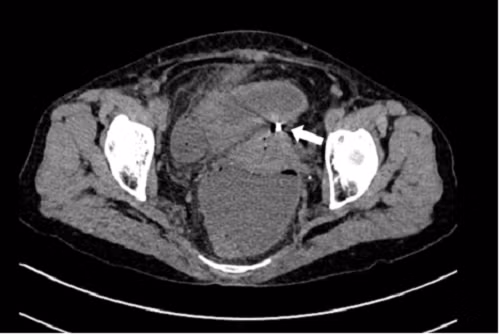

| Hình ảnh chụp cho thấy dụng cụ tử cung xuyên qua thành tử cung vào ruột. Ảnh: Bệnh viện cung cấp/Người Lao Động. |

Khi vào viện, bệnh nhân có biểu hiện viêm phúc mạc như bụng chướng, ấn đau khắp bụng. Chụp cắt lớp vi tính thấy hình ảnh dịch khí tự do trong ổ bụng, tắc ruột cơ năng, dày thành ruột vị trí hố chậu phải và dị vật xuyên thủng đáy tử cung.